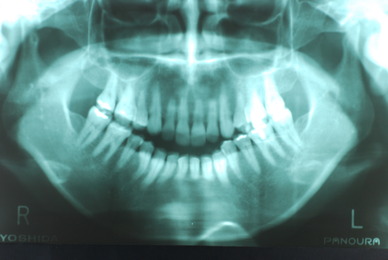

現実を見ればお口の中には“異物”である金歯、銀歯、セラミック、インプラントのオンパレードです。

これ等のものは、異物です。無い方が病気にならず健康でいられるのです。

銀歯の下はばい菌だらけです。こういうのはよくあります。取り残しですね。![treatment_05[1]](https://livedoor.blogimg.jp/netdental/imgs/3/a/3ad019d0-s.jpg)